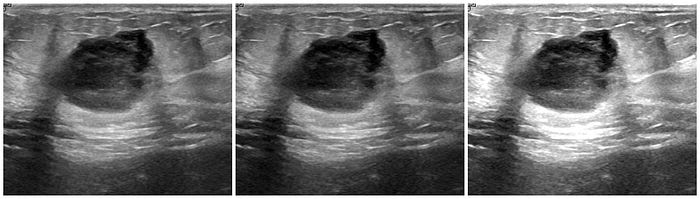

In medical imaging, where precision is crucial, noise should be carefully considered to avoid obscuring important diagnostic details. There are different types of noise modalities that can be introduced, however I'll only be going over the gaussian noise and impulse noise (salt & pepper) in this post.

Gaussian Noise

Gaussian noise is a type of random noise that follows a Gaussian distribution (also known as a normal distribution). In medial images, it can be used to simulate random variations that might occur due to imaging equipment imperfections, sensor noise, or other sources of randomness.

A Gaussian blur is a type of image blurring that involves convolving the image with a Gaussian distribution. This process smoothens the image by reducing high-frequency noise and fine details, which results in a 'blurred' like appearance. The extent of blurring is controlled by the standard deviation (sigma) of the Gaussian distribution. A larger sigma value leads to a stronger blur effect, and a smaller value results in milder blurring.

Much like other augmentation methods, in medical imaging, blur augmentation can simulate the effects of motion or imperfections in imaging devices. For instance, when capturing an MRI or CT scan, patient movement or slight vibrations can cause blurring in the resulting images.

To apply the Gaussian blur, you can use the gaussian_filter() function within the scipy library.